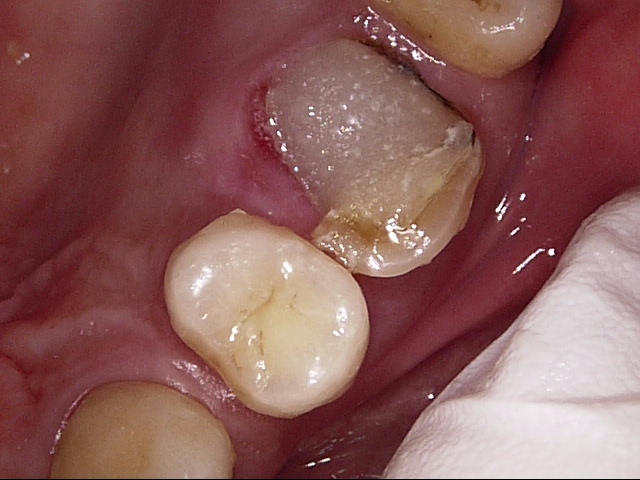

画像で見る歯根破折

神経を抜いた歯は、根尖病巣といわれる歯の根の病気や、歯根破折といって、歯が割れてしまうことで抜歯になることが多いのですが、神経を抜いてからの期間が長いほど、その問題が起きやすいです。

特に、神経のない歯に、歯ぎしりや噛みしめなど強い力が持続的に加わると、歯根破折を起こしやすくなりますので、神経を抜いた時期が早ければ、早いほど、歯を失うリスクが高くなります。